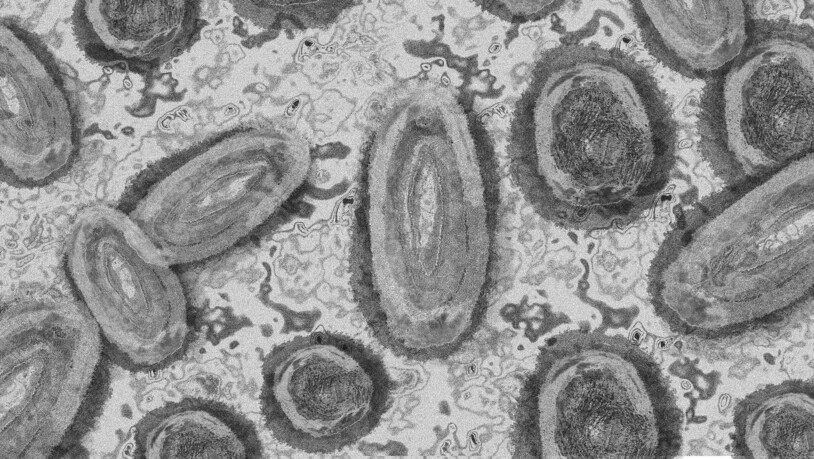

Affenpocken: Das Virus sitzt in Nagetieren, die von Menschen und Affen in Afrika verzehrt oder als Haustiere berührt werden.